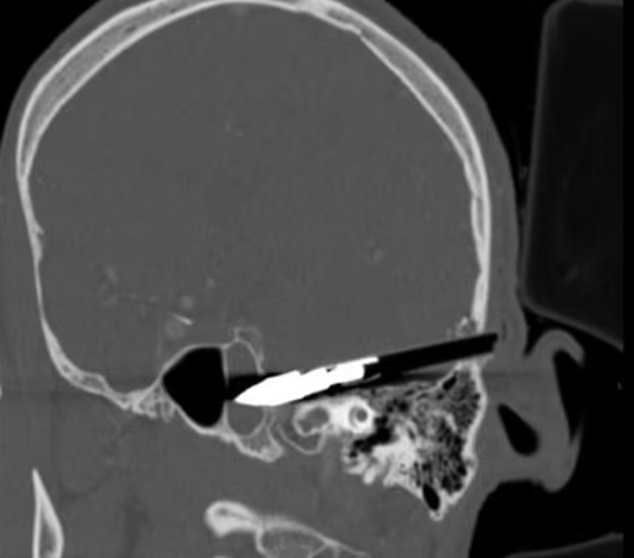

受害人的頭骨被箭射穿。(互聯網)

電腦掃瞄可見Stroie被箭射穿頭骨,箭更深入頭內,直插腦部,幸醫生經漫長手術順利把箭取出,Stroie目前控制左眼及右手手肘有困難、並有複視及焦慮抑鬱問題,算是不幸中的大幸。